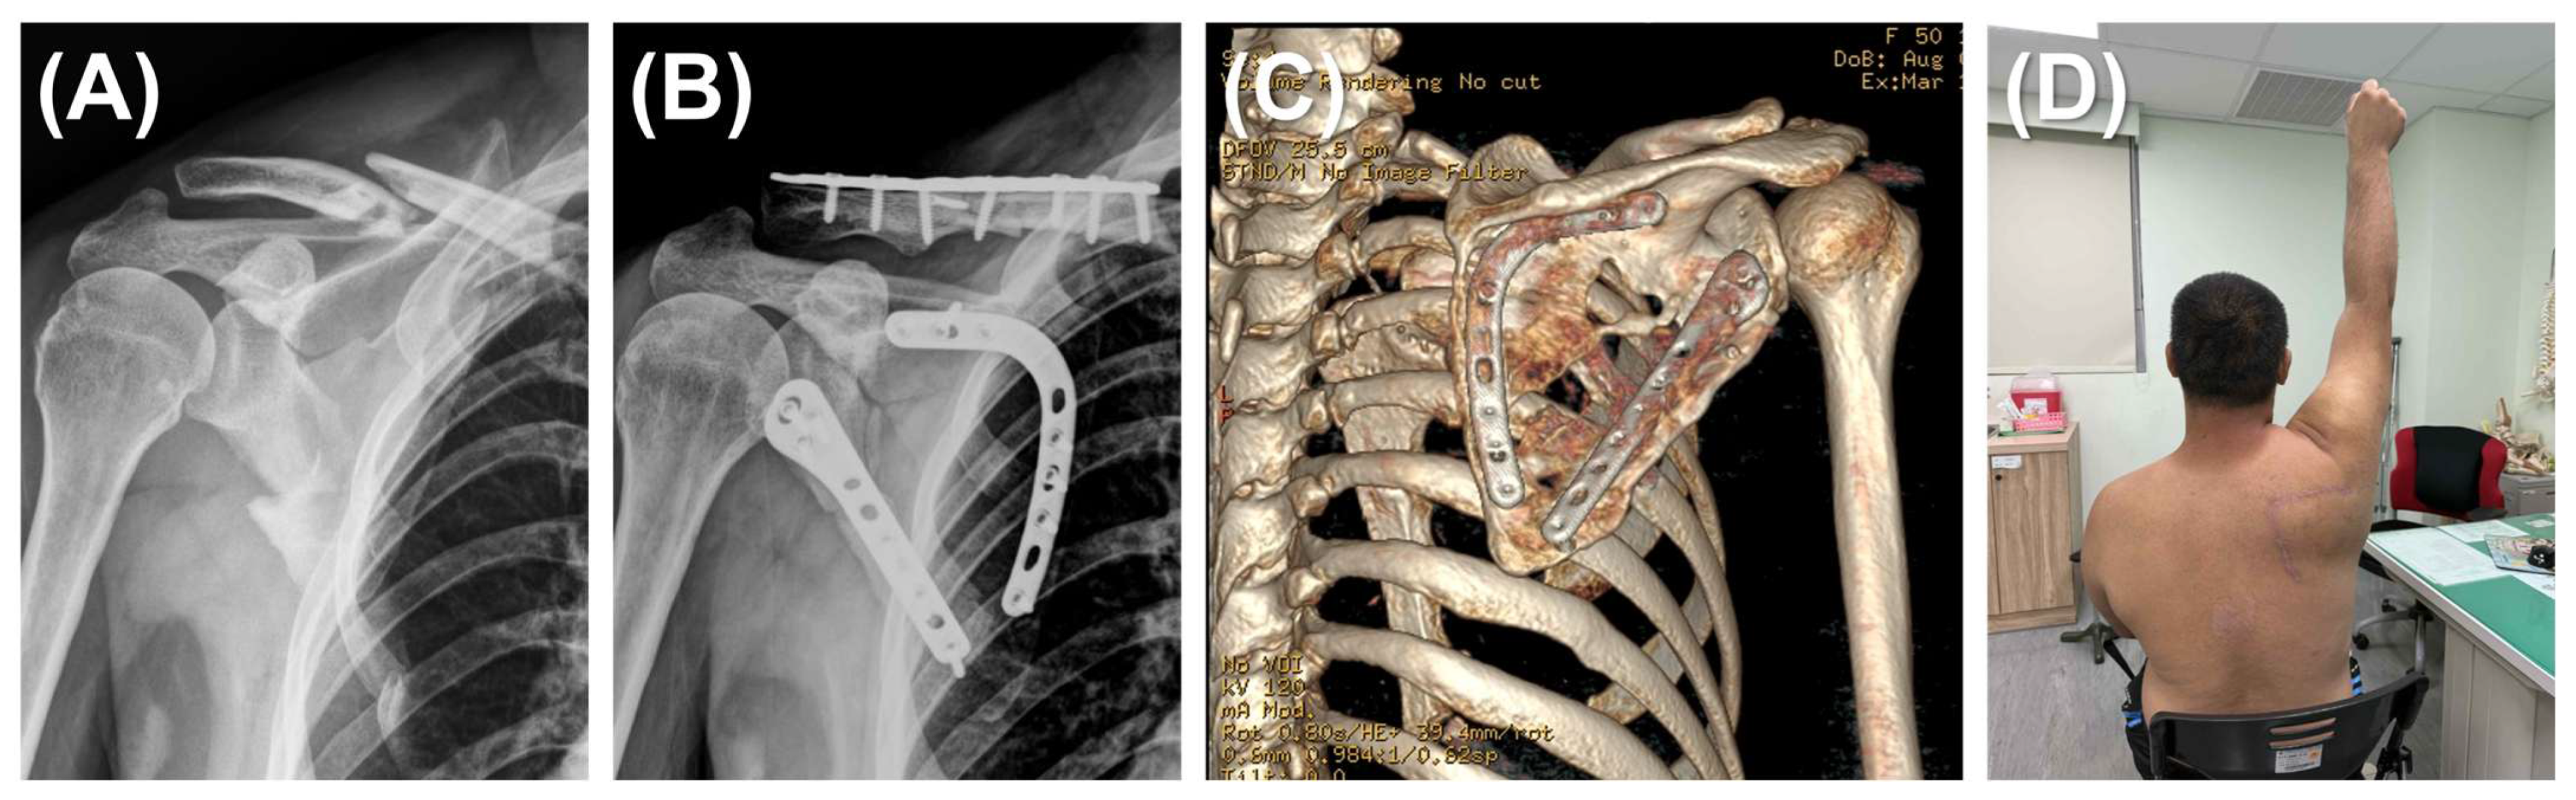

The surgery was carried out with the patients under general anesthesia and positioned in lateral decubitus. In the single plating group, a lateral straight incision was made and the modified Judet approach was generally adopted. The mirror Judet approach was utilized in cases with concomitant rib fractures requiring fixation [19]. The lateral border of the scapula was exposed between the teres minor and infraspinatus muscles, ensuring visualization and protection of the suprascapular nerve and vessels. The lateral border was reduced under direct visualization and fluoroscopic assistance. Fixation was achieved using an anatomical locking plate (Acumed, OR, USA) (Figure 1).

Figure 2. Dual plating for scapular fracture. (A) A 52-year-old man presented with a left scapular fracture (AO/OTA 14B type) and an ipsilateral clavicle fracture. The scapular body exhibited comminution along both the medial and lateral borders. (B) Through a modified Judet approach, the scapular fracture was reduced and stabilized using dual plating (lateral and medial borders). The clavicle fracture was addressed with a standard fixation procedure. (C) A 3D reconstruction at the 16-month postoperative follow-up, after removal of the clavicular implants, demonstrating successful osteosynthesis of the scapular body fracture without malalignment. (D) Clinical photograph of the 52-year-old man at 12 months demonstrating restoration of full active shoulder abduction.